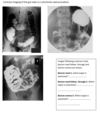

What is A?

Trachea

What is B?

Oesophagus

What is C?

Thoracic duct

What is D?

Left subclavien vein

What is E?

Aortic arch

What is F?

Left bronchi

What is G?

Thoracic aorta

What is H?

Pericardium (cut edge)

What is I?

Oesophageal hiatus

What is J?

Left crus of diaphragm

What is K?

Aortic hiatus

What is L?

Chyle cistern

What is M?

Inferior vena cava

What is N?

Right crus of diaphragm

What is O?

What is P?

What is Q?

What is R?

Tracheobronchial lymph nodes